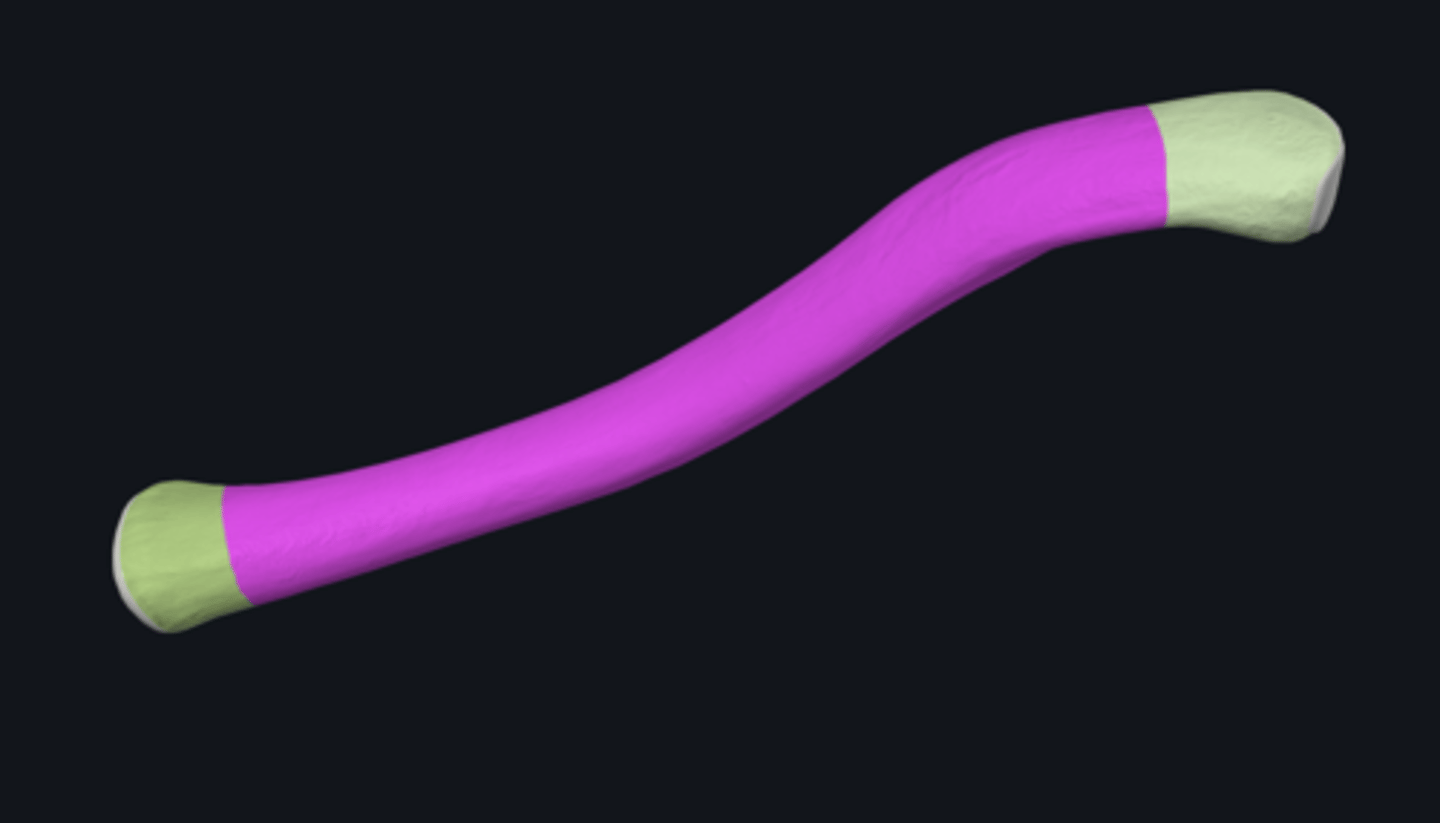

bones of the upper limb

body of ulna

distal part of ulna

proximal part of ulna

anterior border of ulna

anterior surface of ulna

interosseous border of ulna

medial surface of ulna

posterior border of ulna

posterior surface of ulna

supinator crest

articular circumference of head of ulna

articular facet of head of ulna

coronoid process

head of ulna

olecranon process

radial notch

sublime tubercle

supinator fossa

trochlear notch

tuberosity of ulna

ulnar styloid process